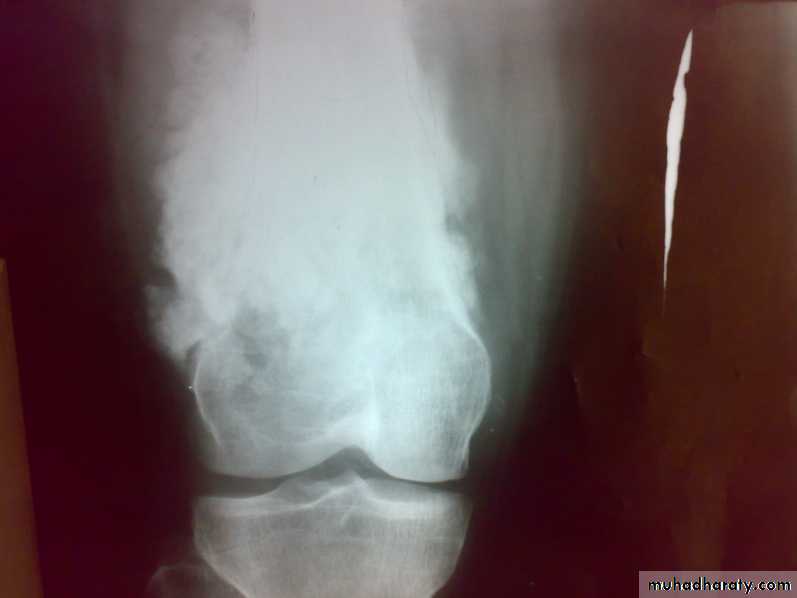

: X-ray are very variable but it show combination of bone destruction and bone formation.

The metaphysis show osteolytic and osteoblastic areas, the cortex is usually perforated and soft tissue shadow may be seen.

There is new bone formation in form of Codman's triangle at periphery of when cortex penetration cause periostium elevation and vertical streaks of calcification in the adjacent soft tissues called sunray appearance.